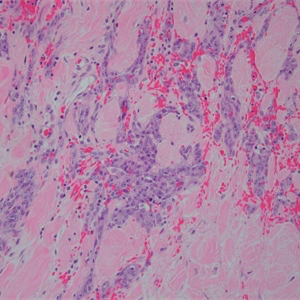

2. 多结节性出血性肿物,细胞形态从梭形至上皮样不等;

4. 肿瘤性血管形态不规则,通过血窦结构互相连通,并破坏浸润周围组织,有些区域血管的肿瘤性内皮细胞过多,形成出芽、突起或乳头;

5. 肿瘤细胞异型性明显,恶性程度高,核分裂象易见,瘤组织具有显著侵袭性;